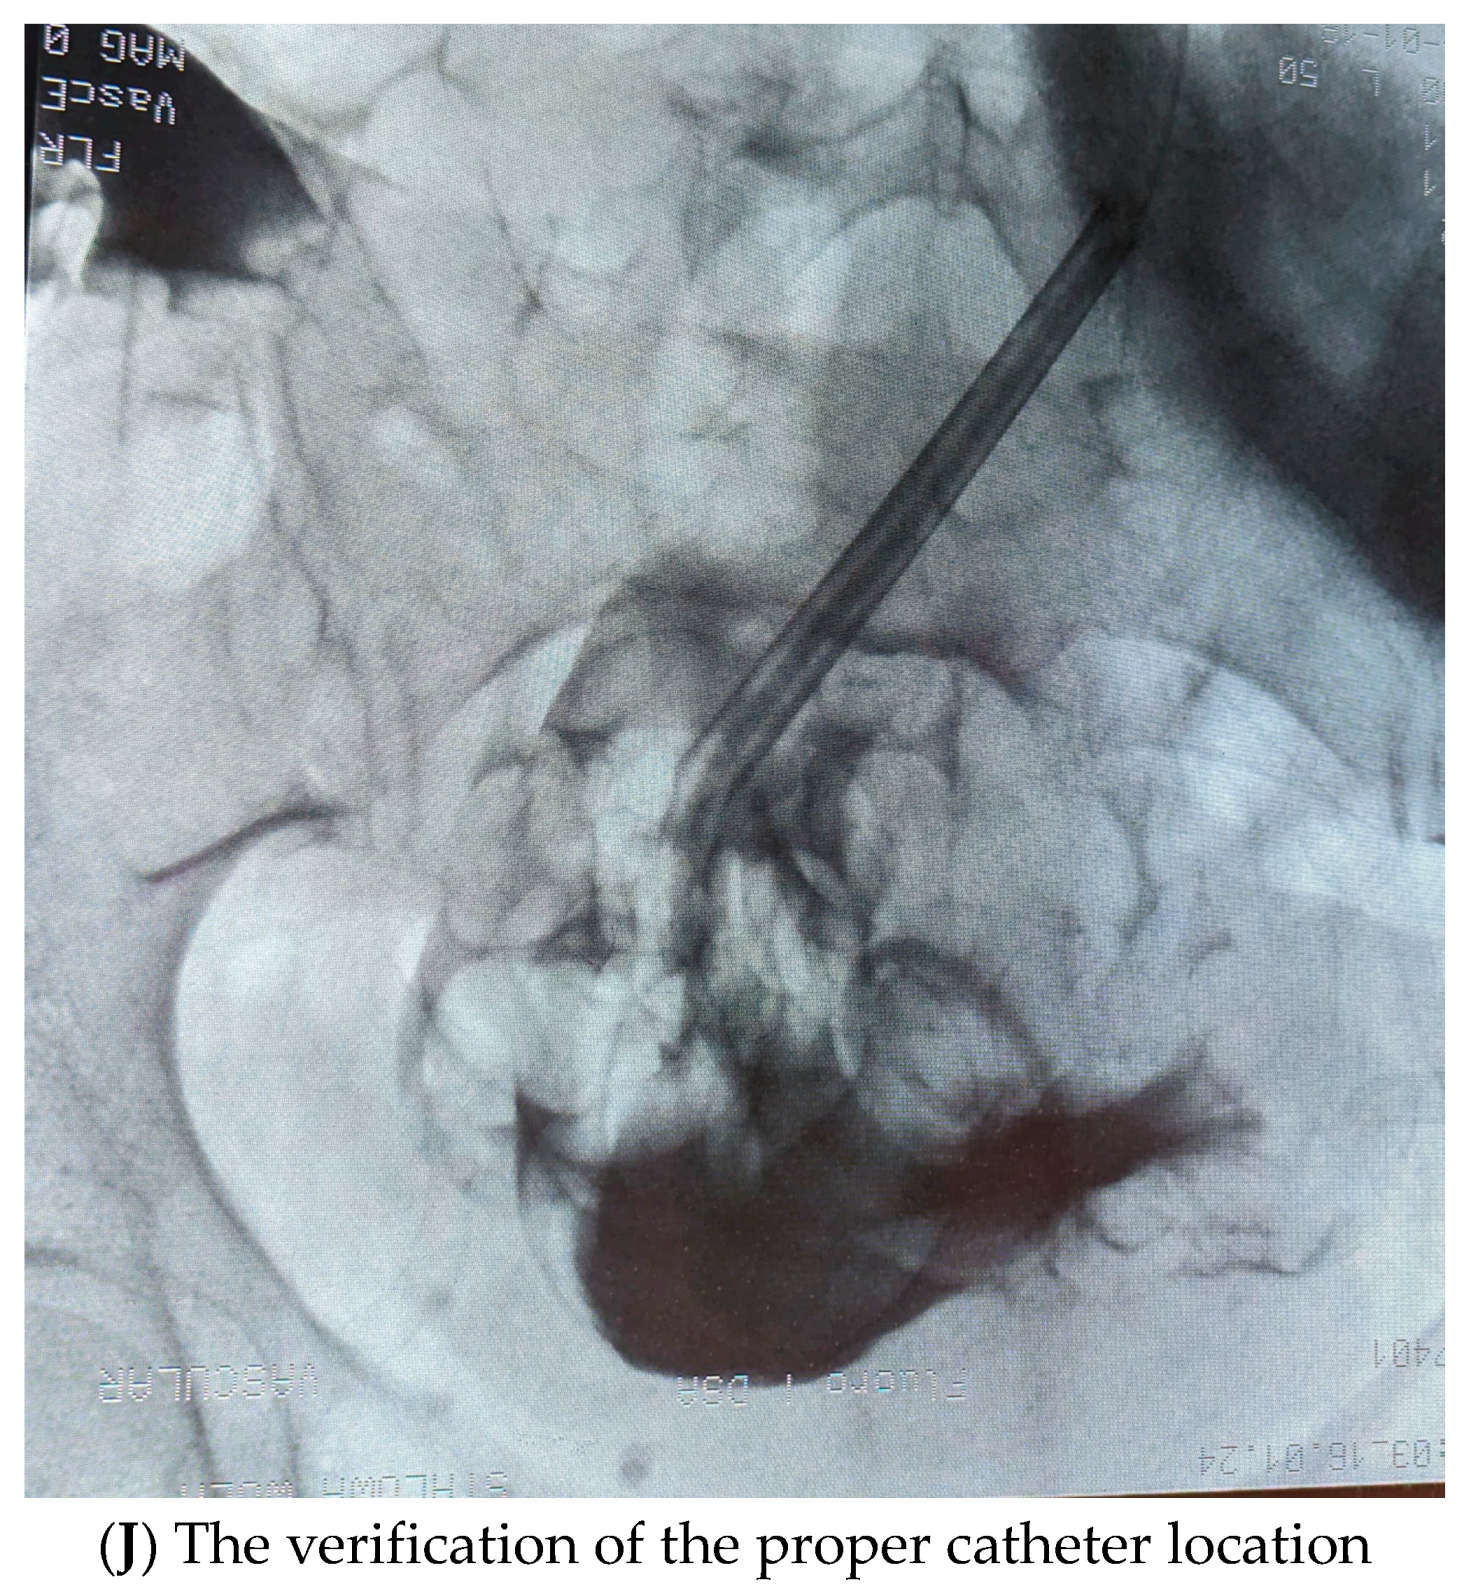

- (6)

- The coiled catheter was then placed on the stylet (double-cuff Tenckhoff coiled catheter—Covidien, Mansfield, MA, USA), advanced through the sheath to the peritoneal cavity (Figure 1I). The catheter tip is placed deeply into the recto-vesical space in men and the recto-uterine space in women, which is the most gravity-dependent region where dialysate fluid accumulates, potentially providing the best drainage of dialysis fluid. To verify the proper location, the fluoroscopic location was used (Figure 1J). The internal catheter cuff was placed next to fascia. Next, a catheter flow test was performed to check the catheter function (300–500 mL of peritoneal fluid was administered and drained).